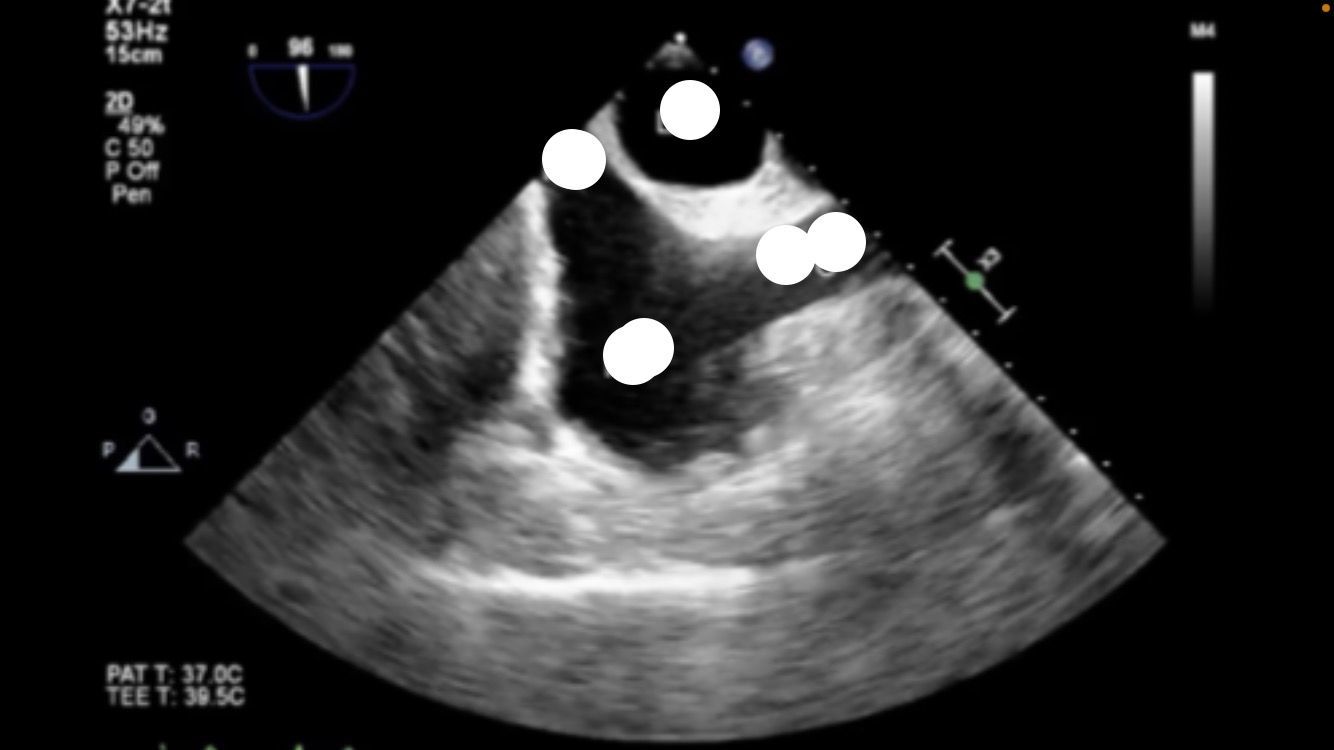

Bicaval view

air embolism in right atrium

view?

PFO

mid-esphageal bicaval